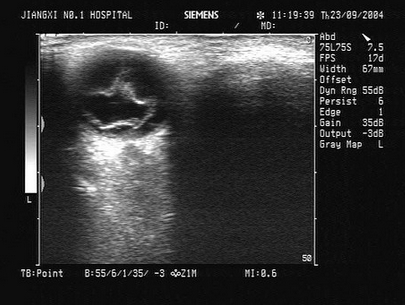

23、单项选择题

患者男46岁,既往有胆囊结石病史,上腹部疼痛不适年余,加重1个月,皮肤、巩膜轻度黄染,B超检查如图所示,根据超声声像图,诊断为()